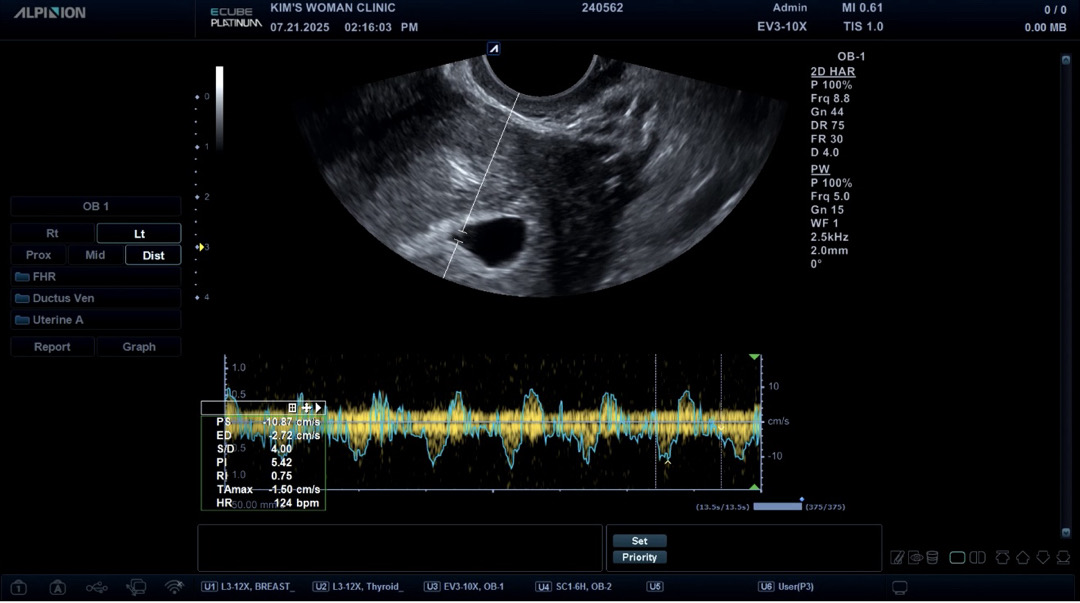

오늘 오른쪽난소에 물혹 때문에 아파서 진료갔다가 심소 듣고왔어요!!저번주 토요일에 방문했을 때 빨리가서 못 들었는데 이틀만에 컸네요🥹 6주2일차 됐습니다!